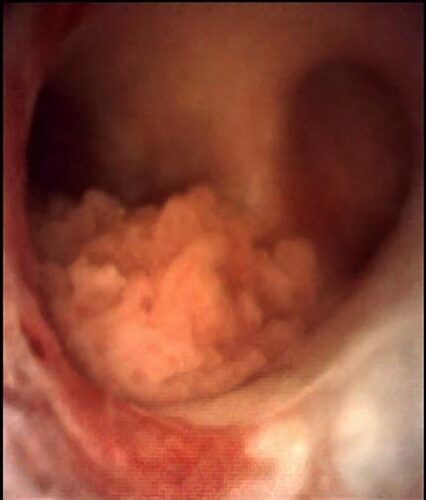

El diagnóstico endoscópico del CVUA mediante ureterorrenoscopía flexible (URS flex) incluye la visualización directa del tumor y la recolección de muestras para estudio citológico e histopatológico. Los ureteroscopios flexibles actuales permiten acceso primario e inspección de todo el tracto superior en hasta el 95% de los pacientes28. El diseño y calibre de la punta, el diámetro del cuerpo y la capacidad de deflexión de los instrumentos influyen en la probabilidad de un acceso exitoso. Los ureteroscopios flexibles de menor diámetro (cuerpo <8Fr) siguen siendo aquellos de fibra óptica. Los ureteroscopios flexibles digitales, tanto reutilizables como desechables, proporcionan una calidad óptica superior, pero a costa de una deflexión distal menos versátil y un calibre algo mayor (cuerpo 8,4 – 9,9Fr, dependiendo del fabricante/modelo)29,30.

La técnica de URS flex para el diagnóstico de CVUA merece algunas consideraciones especiales (ver video adjunto). Cada vez que sea posible debería intentarse una inspección inicial “sin tocar” el uréter previamente. Es decir, sin introducir una guía hasta la pelvis renal antes de iniciar la ureteroscopía. Esto permite visualizar lesiones a lo largo de todo el uréter y en el sistema colector intrarrenal sin el artefacto o hemorragia que potencialmente pudiera causar la manipulación previa (Figura 3). Para acceder al tracto superior generalmente es necesario, eso sí, al menos dilatar el orificio ureteral y el uréter distal con un ureteroscopio semirrígido o un dilatador (secuencial, coaxial o balón) sobre una guía apenas insinuada. No existe evidencia suficiente para recomendar el uso rutinario de vaina de acceso ureteral, aunque ésta puede facilitar la toma de múltiples muestras para biopsia37.

Durante la URS flex diagnóstica debería registrarse detalladamente el hallazgo de lesiones sospechosas, indicando localización, número y tamaño aproximado. Además es necesario describir su aspecto (plano, sésil, pediculado) y la impresión macroscópica de corresponder a una lesión de bajo o alto grado. Idealmente debe tomarse muestra para citología localizada, ya sea mediante lavado (con jeringa y solución salina) o cepillo para citología, cuya punta luego se corta y envía a análisis. Las lesiones sospechosas deberían ser biopsiadas con pinzas de biopsia endoscópicas o con un canastillo de nitinol de 4 hebras. Esto resulta relativamente sencillo con lesiones papilares y de mayor volumen, pero puede ser bastante dificultoso ante lesiones planas, muy pequeñas o en localizaciones que no permiten abordar la lesión de frente. De todos modos, el tamaño de las muestras obtenidas habitualmente es muy pequeño, por lo que es recomendable tomar más de una muestra. Existen diferentes pinzas de biopsia disponibles en el mercado, siendo posible la obtención de muestras de mayor tamaño con ciertas pinzas que requieren ser cargadas en forma retrógrada en el ureteroscopio38.